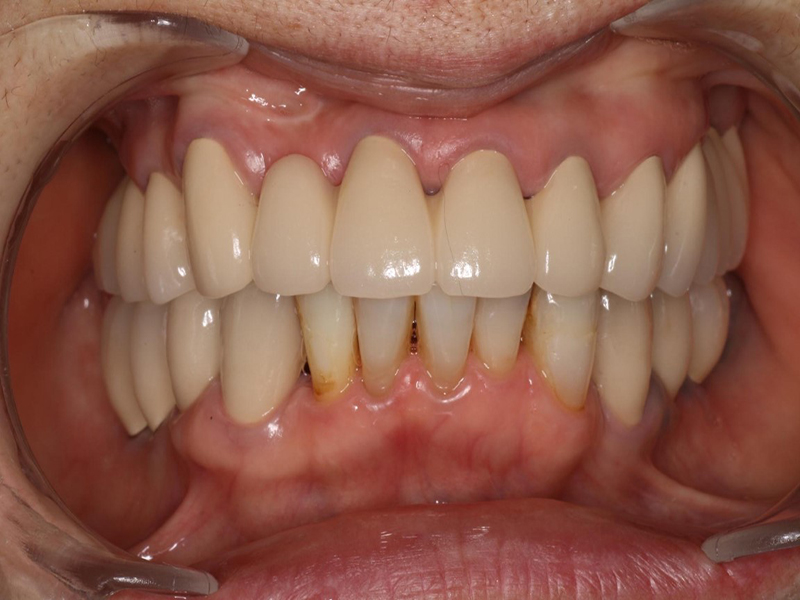

治療終了時口腔内写真